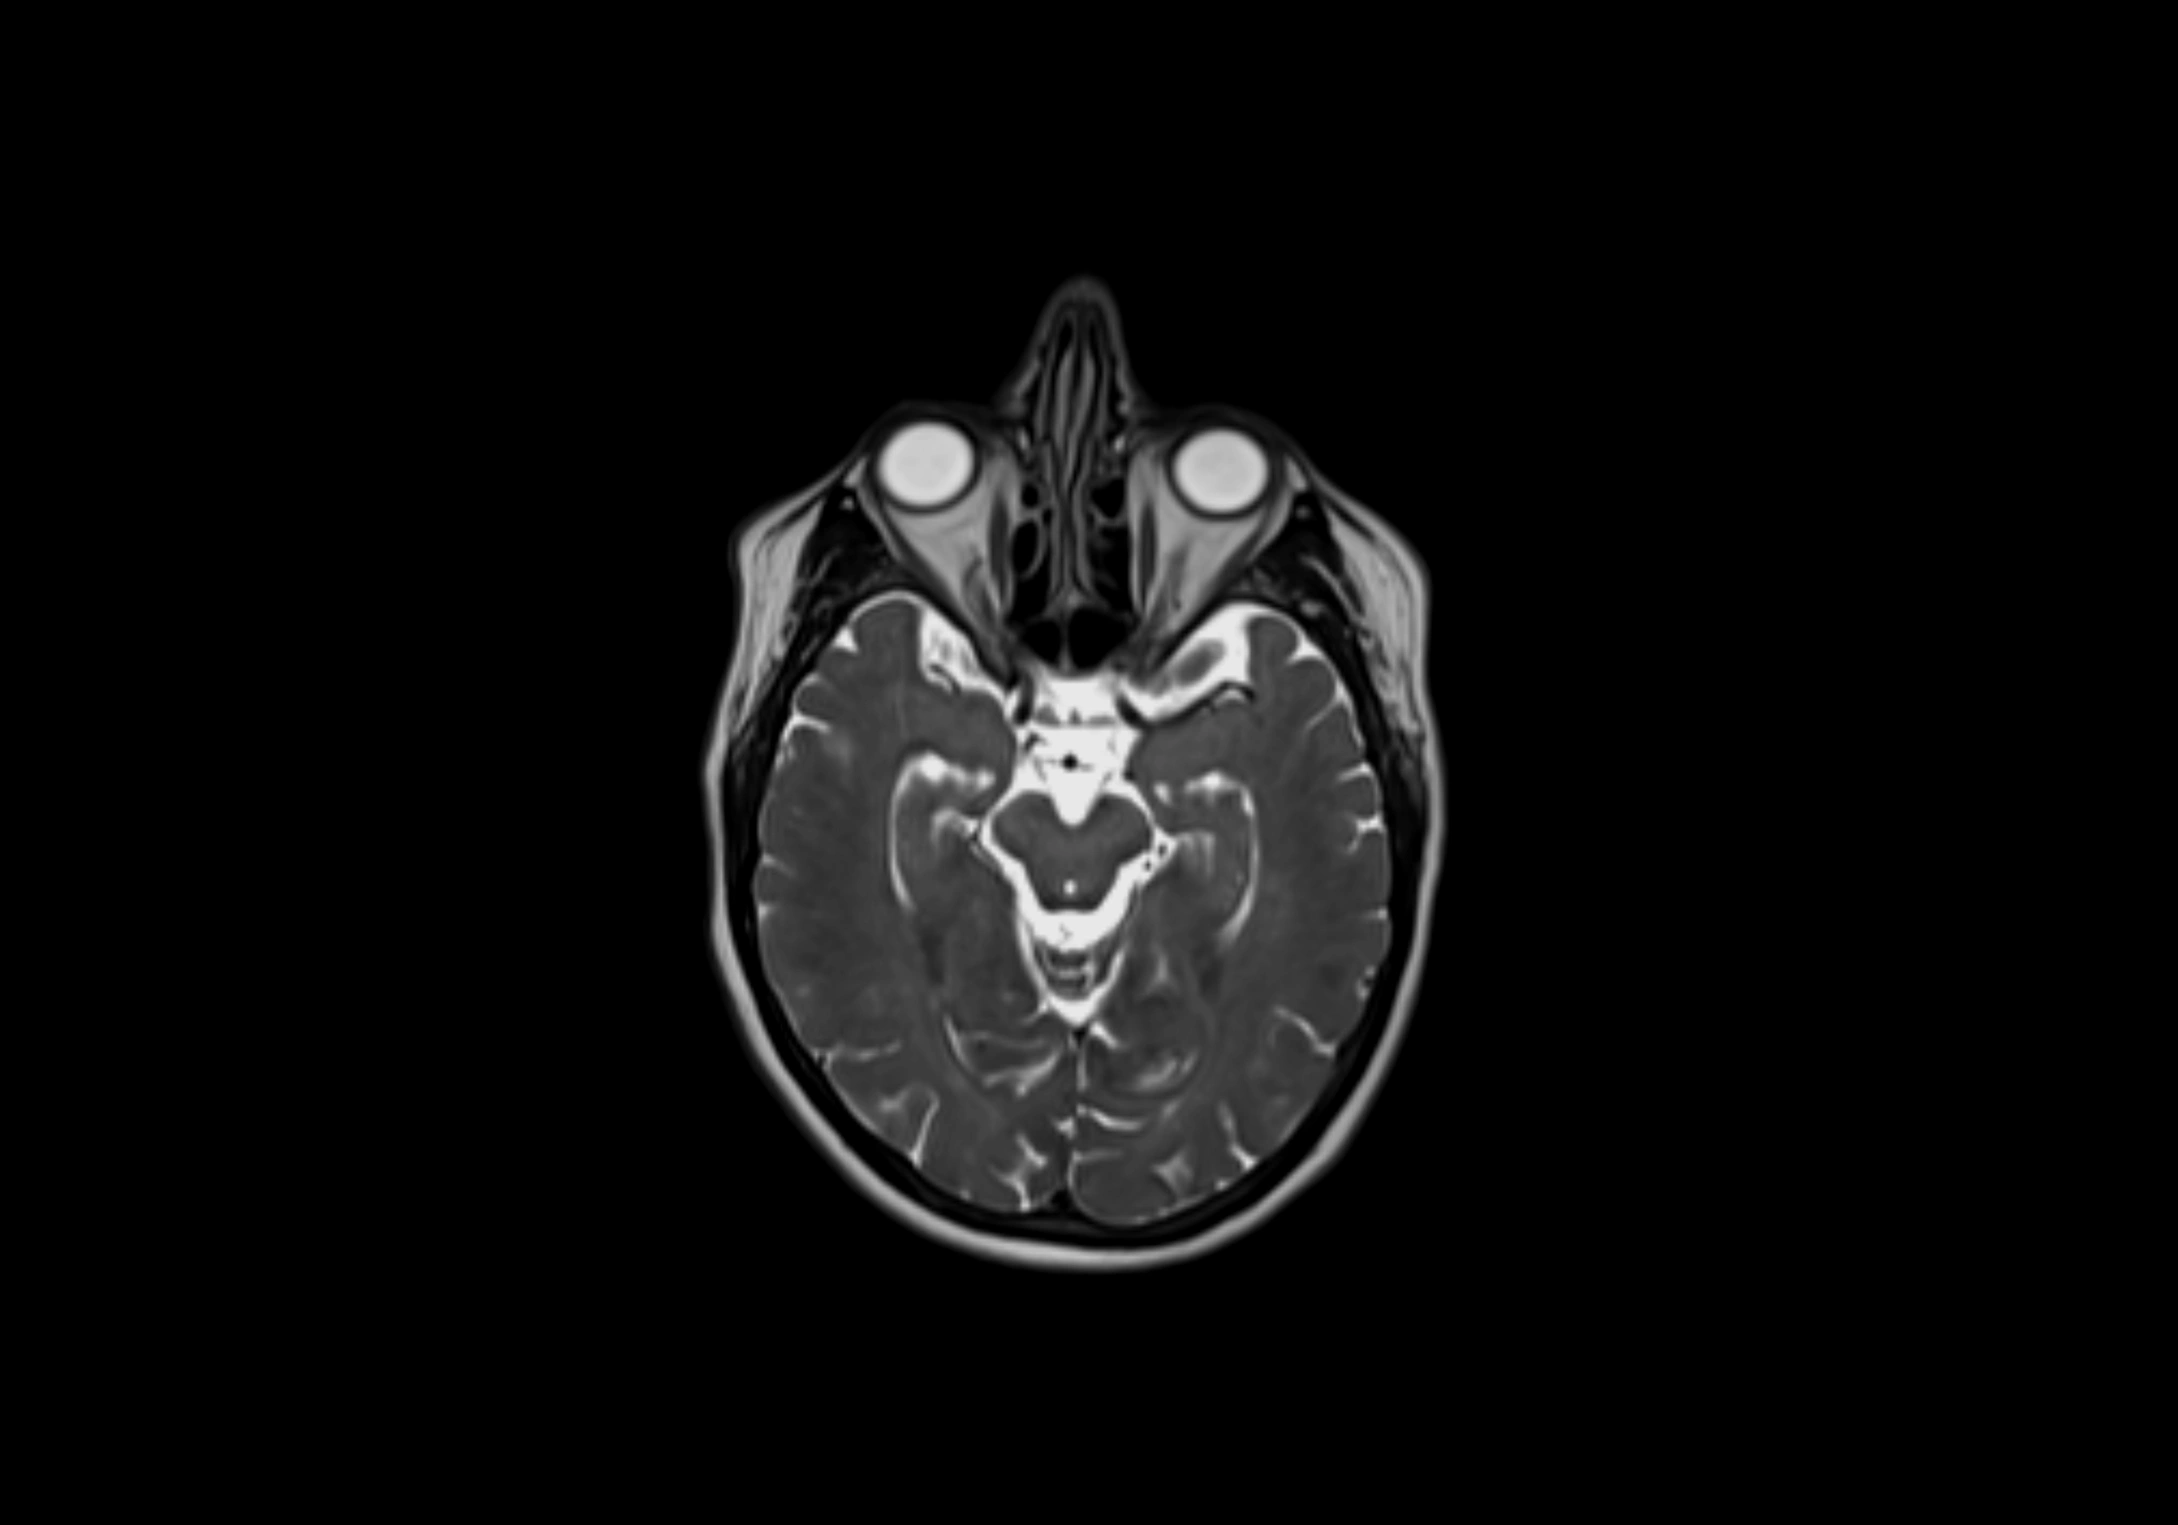

MRI Appearance

T2-weighted images:

• Nodes show intermediate signal, with surrounding fat bright

• Useful for detecting edema, inflammation, or infiltration

• Fatty hilum may appear slightly hyperintense relative to cortex

MRI images

image